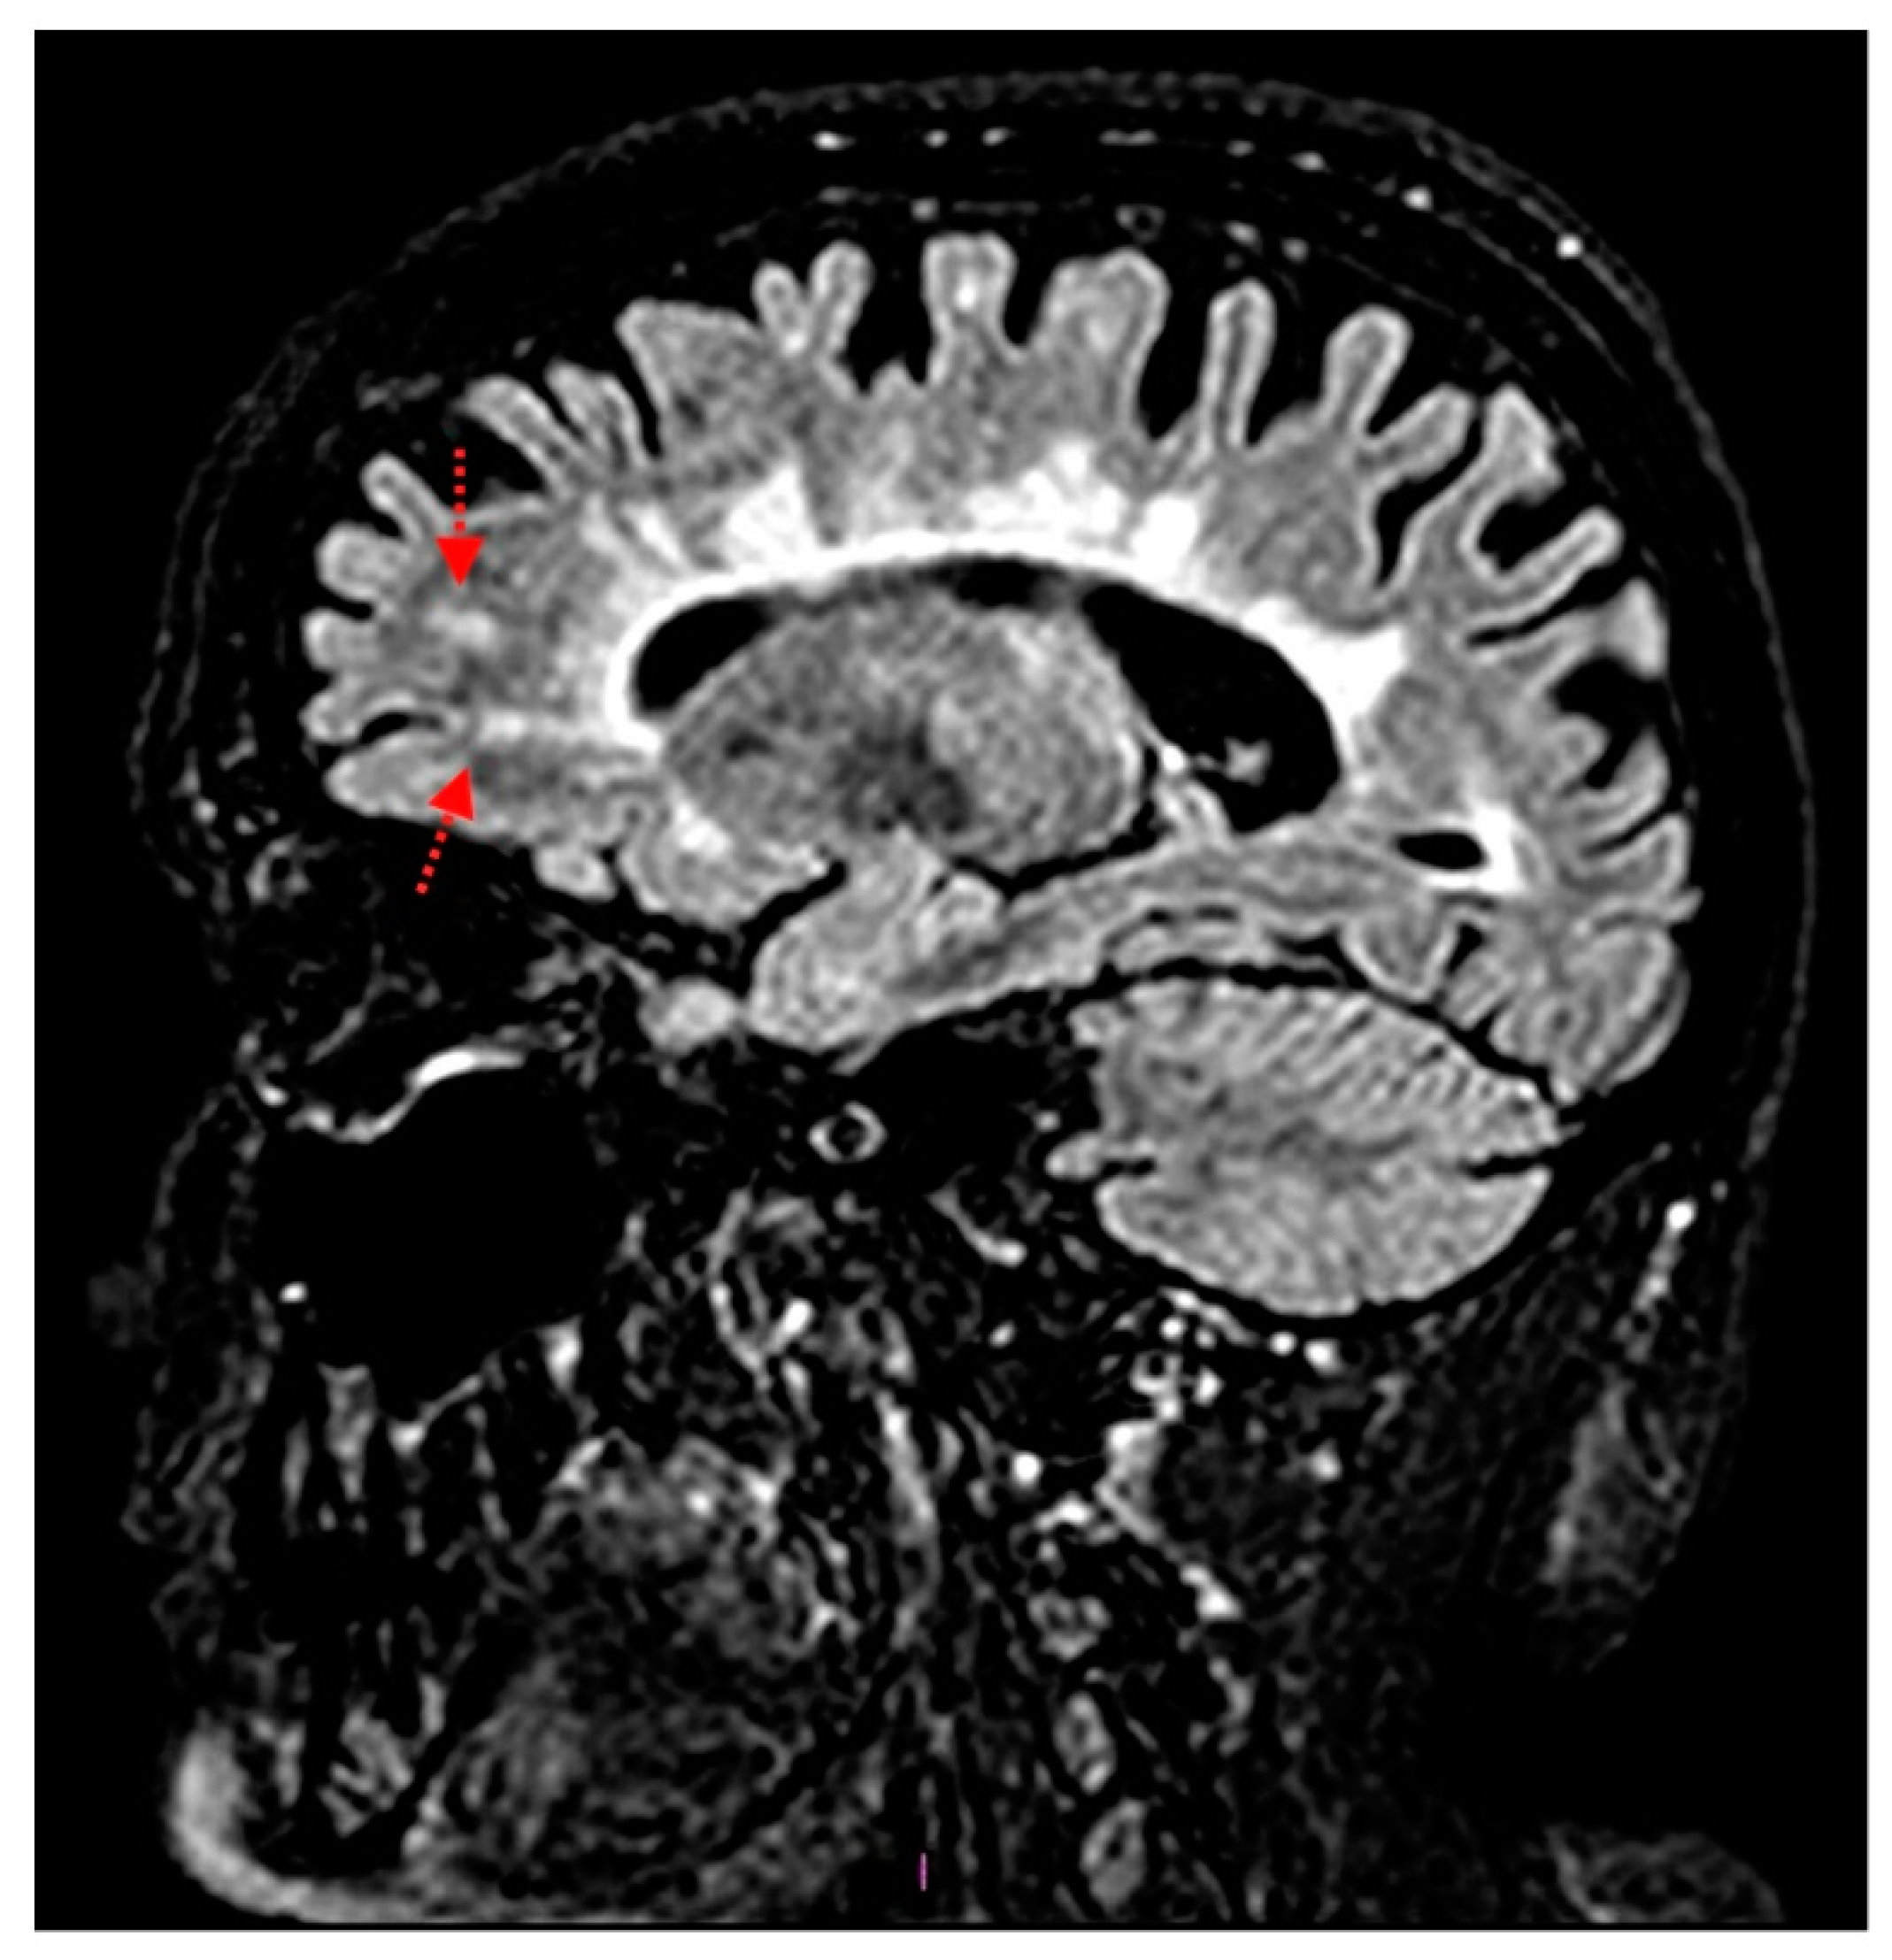

Figure 2.

Magnetic resonance imaging on the sagittal fluid attenuated inversion recovery (FLAIR) sequence of the brain, demonstrating the two demyelinating subcortical left frontal lesions (red arrows), resulting from the enhancing ones at the disease onset.

These lesions, partially confluent and not exceeding three metamers in length, were not associated with tumefactive cervical shape and fulfilled the radiological criteria for MS lesions, as expected. No new brain lesions were detected and a total intracranial volume (TIV) of 1328.8 mL was calculated using Siena software. Thus, the diagnosis of steroid-refractory relapsed MS on Fingolimod treatment was posed, DFPP therapy was indicated, and FTY was discontinued. In Figure 1C it could be also glimpsed two subcortical hyperintense left frontal areas, resulting from enhancing lesions at the disease onset. The demonstration of these lesions assumes an important diagnostic role in the present case, and they are better represented in Figure 2.